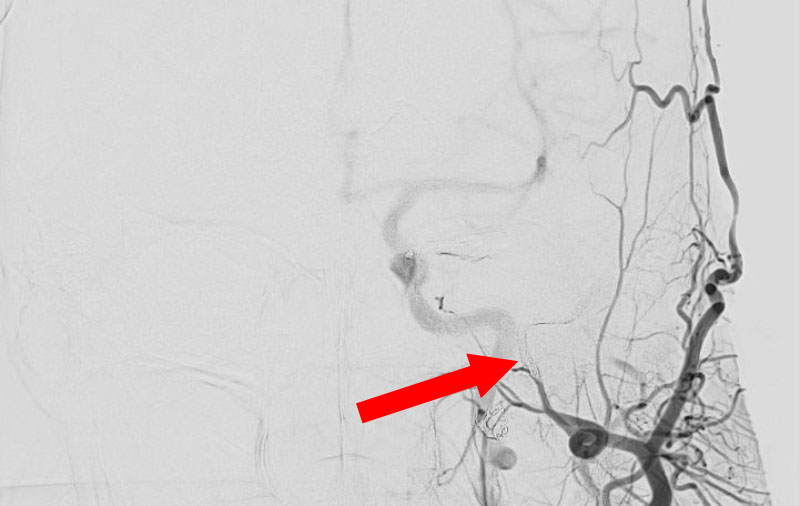

'25年11月

くも膜下出血

破裂性内頚動脈解離

40代

救急外来

No.1594 手術前

No.1594 手術中

No.1594 手術後